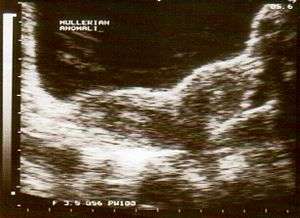

Ultrasound showing didelphys

Uterus didelphys (sometimes also uterus didelphis) represents a uterine malformation where the uterus is present as a paired organ when the embryogenetic fusion of the Müllerian ducts fails to occur. As a result, there is a double uterus with two separate cervices, and rarely a double vagina as well. Each uterus has a single horn linked to the ipsilateral fallopian tube that faces its ovary.

Helpful techniques to investigate the uterine structure are transvaginal ultrasonography and sonohysterography, hysterosalpingography, MRI, and hysteroscopy. More recently 3-D ultrasonography has been advocated as an excellent non-invasive method to evaluate uterine malformations.[3]